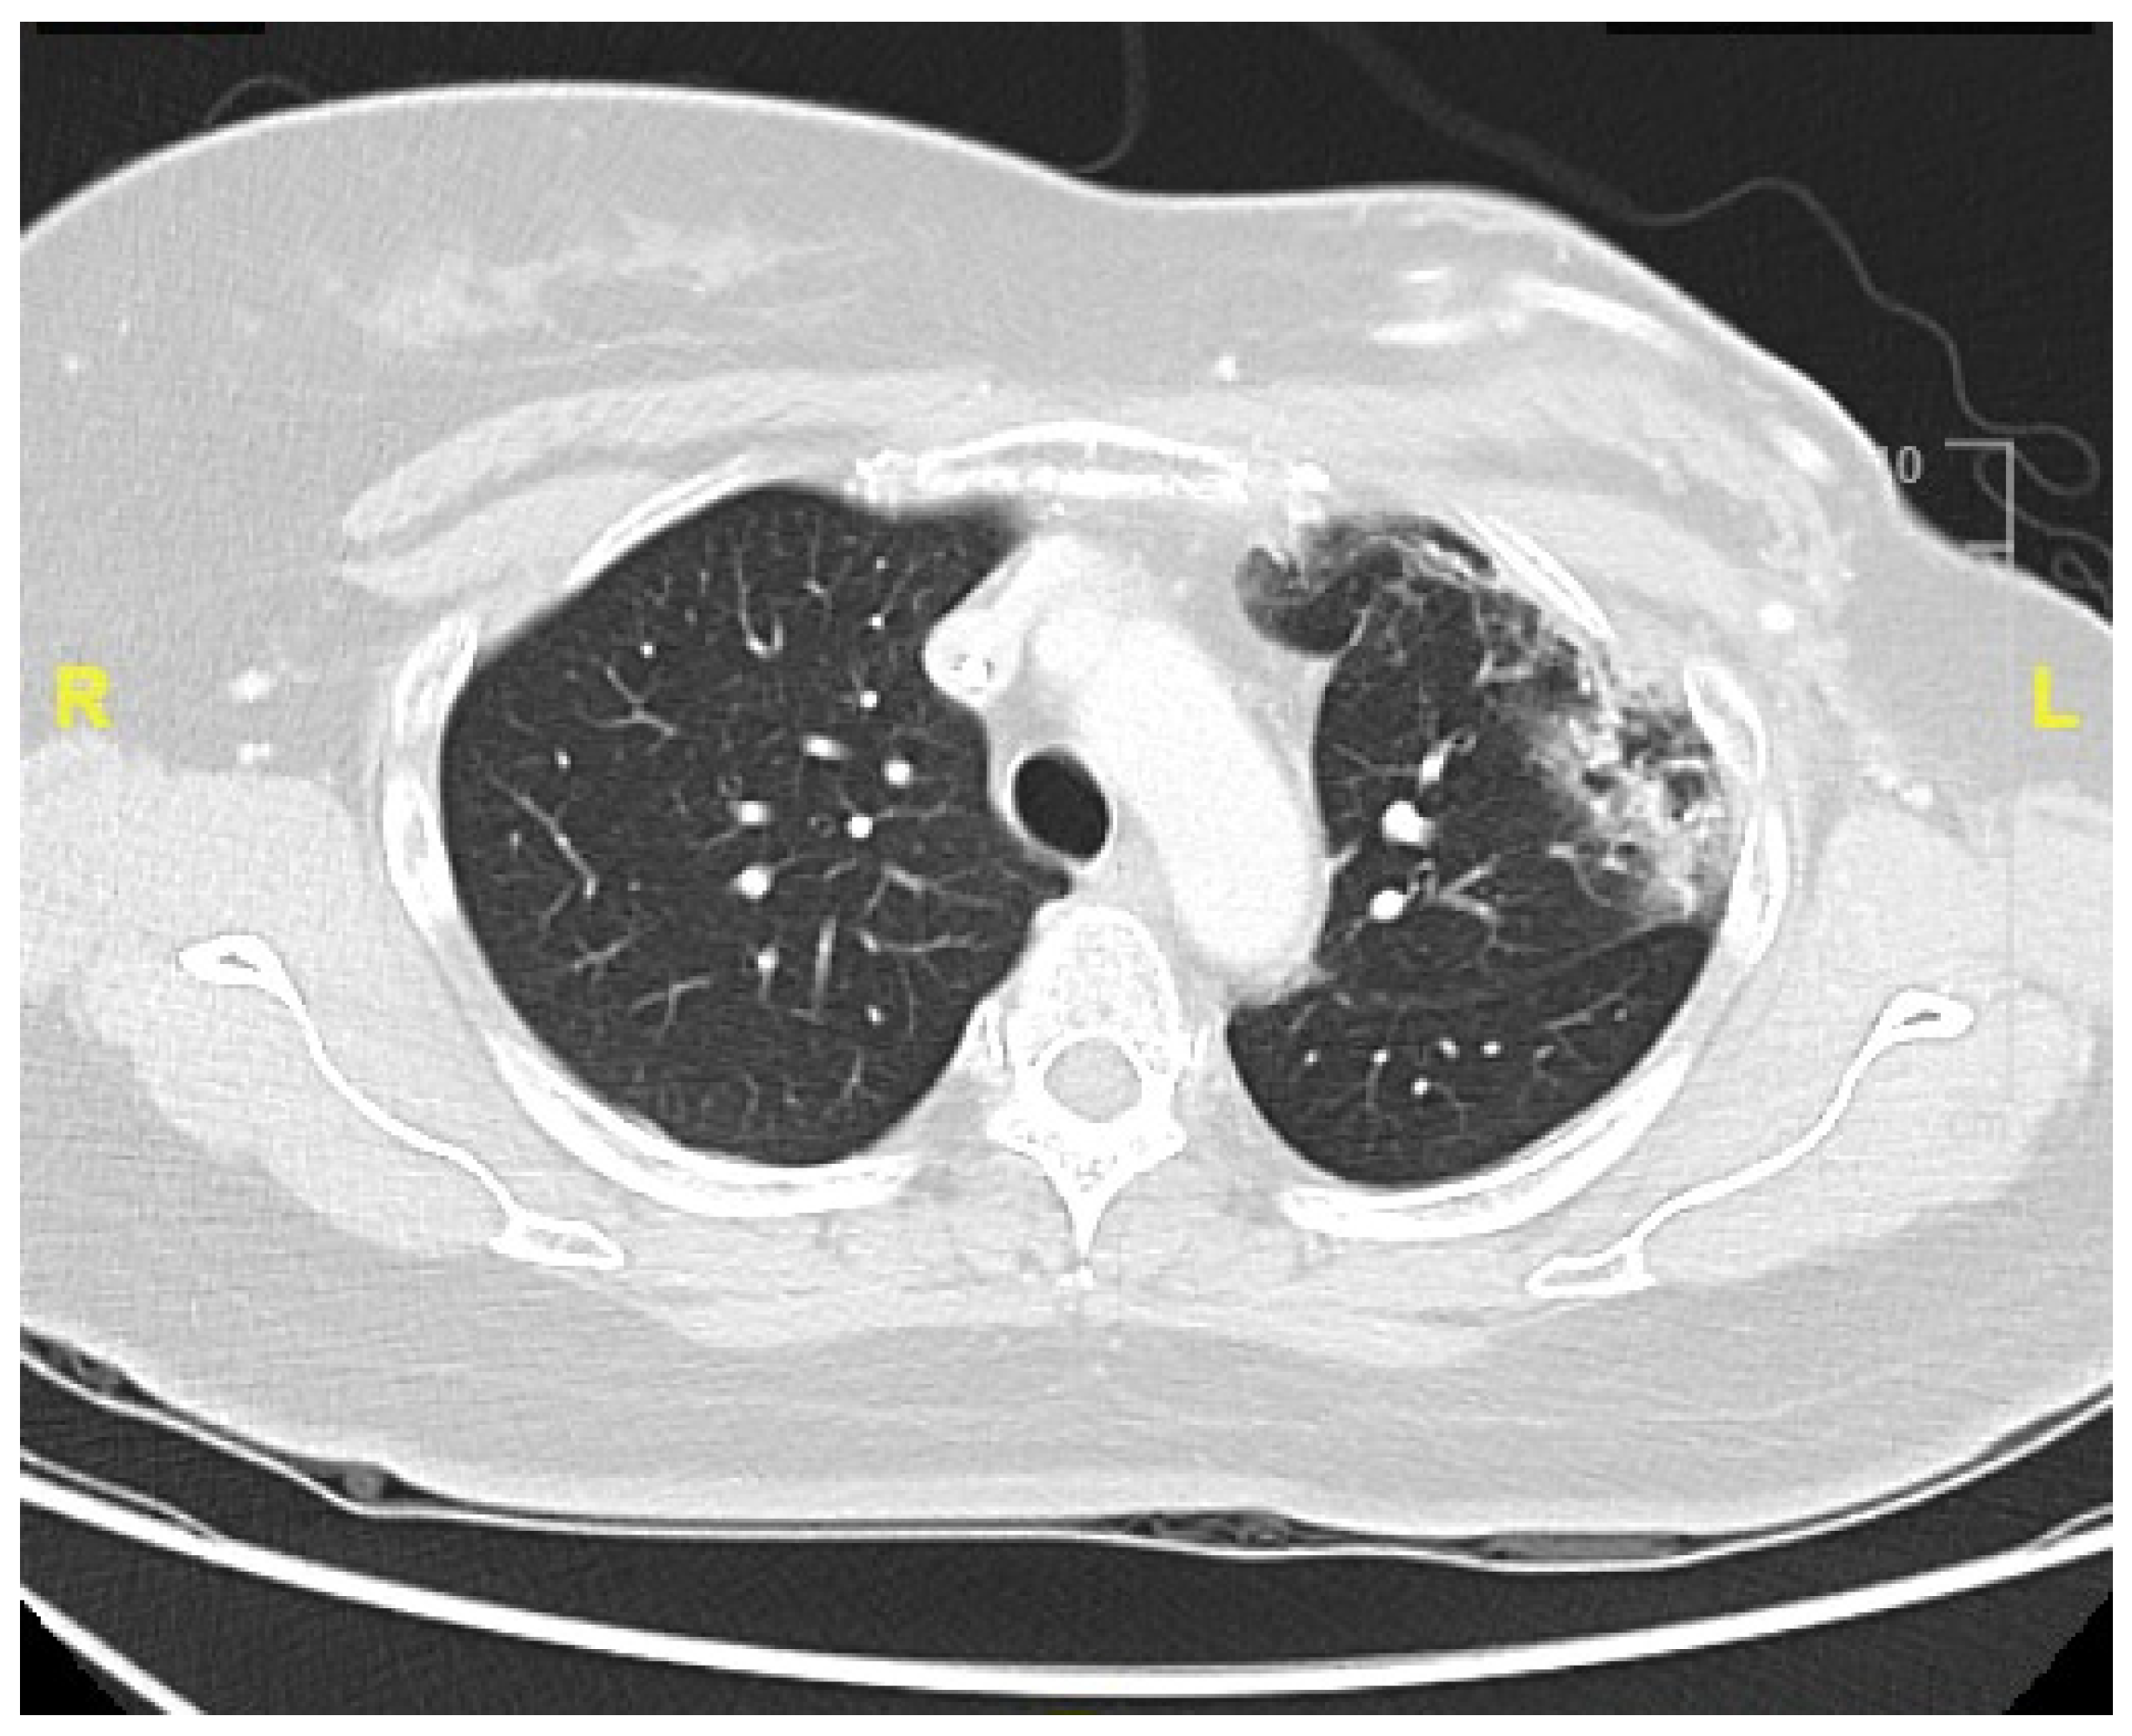

3. Case